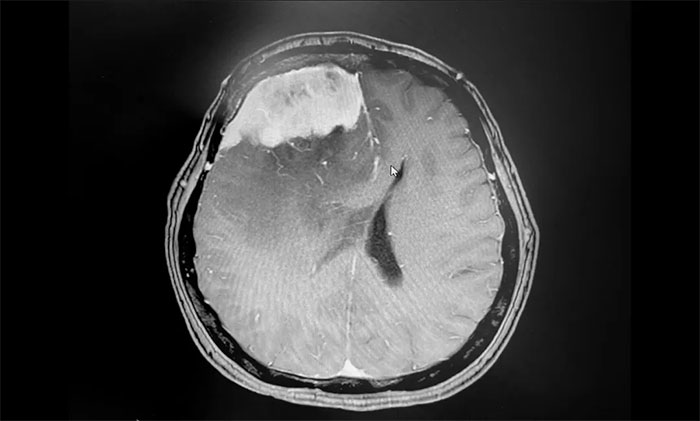

▲ 术后影像,肿瘤已切除

手术顺利完成后,患者生命体征平稳,安返监护病房。留取病理标本送检,确定为脑膜上皮型脑膜瘤(WHO I级),为良性肿瘤。

▲ 病理分析确定为脑膜上皮型脑膜瘤(WHO I级)